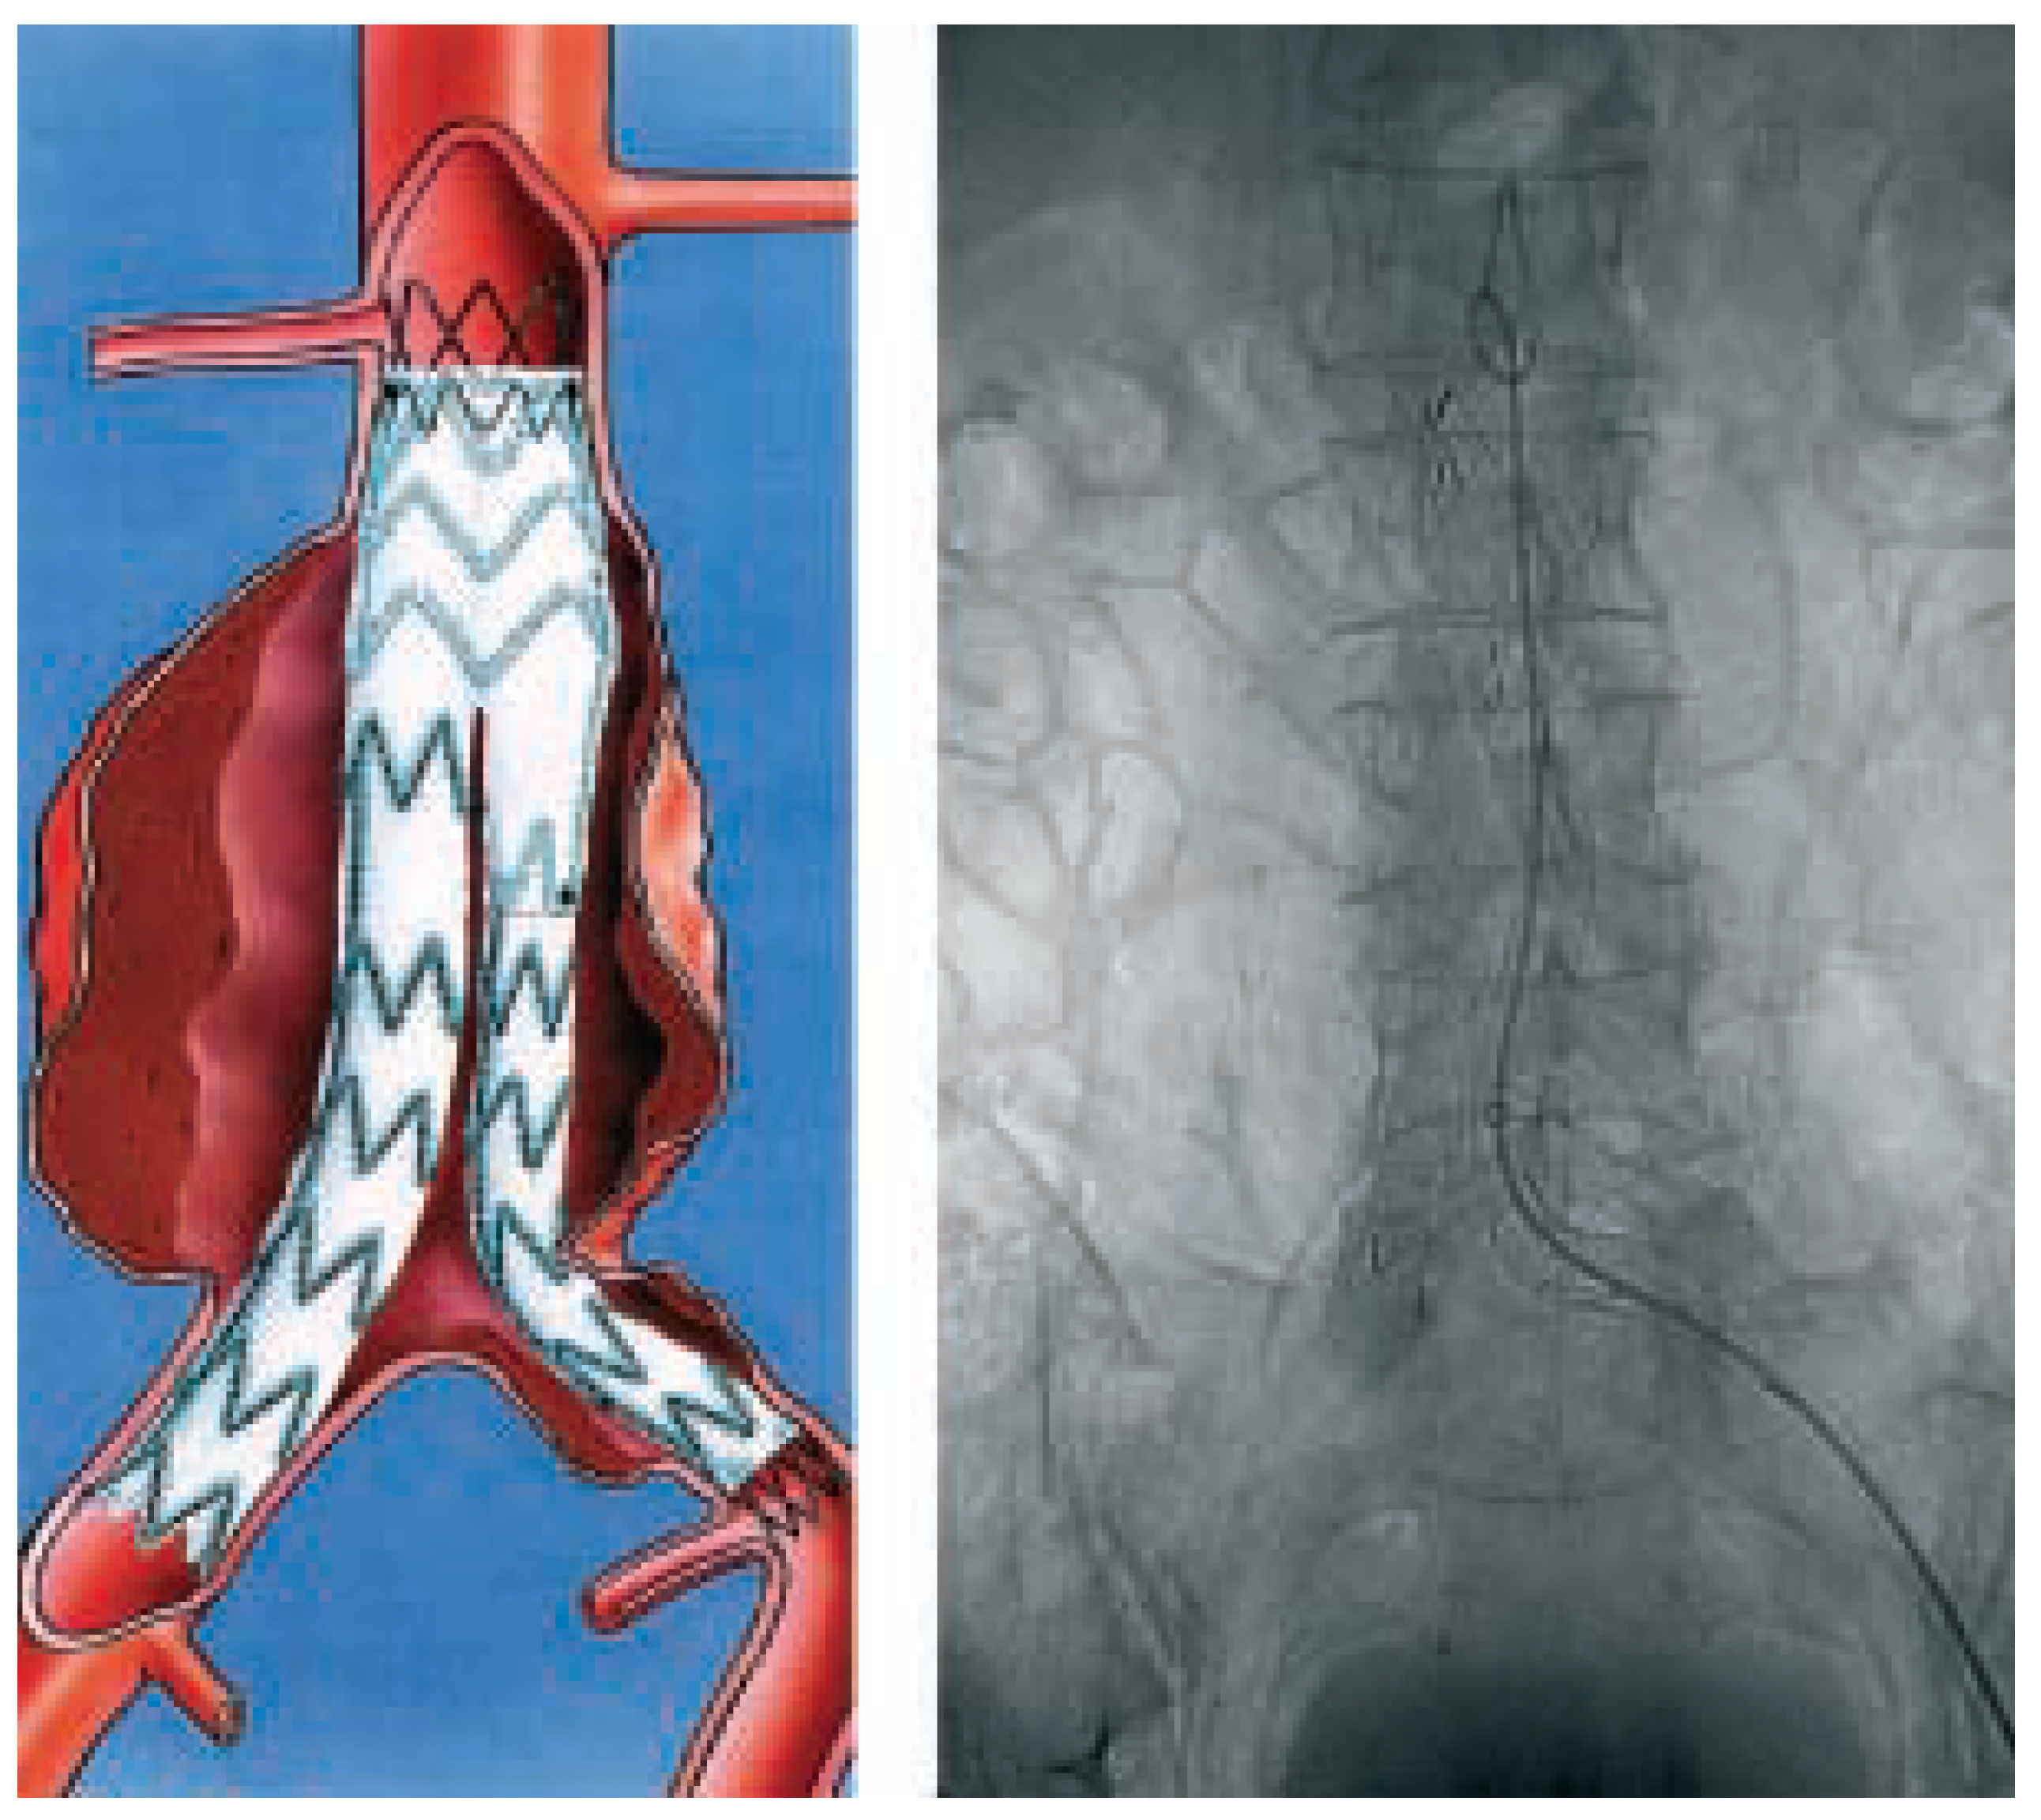

- Adraensen, M.E.; Bosch, J.L.; Halpern, E.F.; Hunink, M.G.; Gazelle, G.S. Elective endovascular versus open surgical repair of abdominal aortic aneurysms: systematic review of shortterm results. Radiology 2002, 224, 739–747. [Google Scholar] [CrossRef] [PubMed]

- Bosch, J.L.; Kaufman, J.A.; Beinfeld, M.T.; Adriaensen, M.E.; Brewster, D.C.; Gazelle, G.S. Abdominal aortic aneurysms: cost-effectiveness of elective endovascular and open surgical repair. Radiology 2002, 225, 337–344. [Google Scholar] [CrossRef] [PubMed]

- Dake, M.D.; Miller, D.C.; Semba, C.P.; Mitchell, R.S.; Walker, P.J.; Liddell, R.P. Transluminal placement of endovascular stentgrafts for the treatment of descending thoracic aortic aneurysms. N Engl J Med 1994, 331, 1729–1734. [Google Scholar] [CrossRef] [PubMed]

- Criado, F.J.; Clark, N.S.; Barnatan, M.F. Stent graft repair in the aortic arch and descending thoracic aorta: a four-year experience. J Vasc Surg 2002, 36, 1121–1128. [Google Scholar] [CrossRef] [PubMed]

- Scharrer-Pamler, R.; Kotsis, T.; Kapfer, X.; Görich, J.; Orend, K.H.; Sunder-Plassmann, L. Complications after endovasculat treatment of thoracic aortic aneurysms. J Endovasc Ther 2003, 10, 711–718. [Google Scholar] [CrossRef] [PubMed]

- Rehders, T.C.; Chatterjee, T.; Ince, H.; Petzsch, M.; Kische, S.; Nienaber, C.A. Endovascular therapy for pathology of the descending thoracic aorta: current status and indications. Kardiovaskuläre Medizin 2005, 8, 89–96. [Google Scholar]

- Schmidli, J.; Do, D.; Triller, J.; Baumgartner, I.; Berdat, P.; Widmer, F.; et al. Aless invasive approach to repair the aortic arch using a “partial” or “complete debranching” of the supraaortic vessels. Kardiovaskuläre Medizin 2005, 8, 82–88. [Google Scholar]